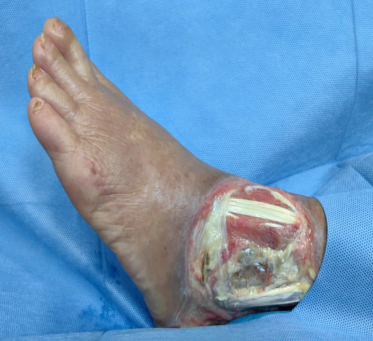

糖尿病足的特色治療—Masquelet技術+側方骨膜牽張技術+NPWT+HADM聯合自體薄層皮“一步法”復合移植技術

下肢動脈閉塞癥—潰瘍、骨髓炎(保趾成功)NPWT+雙層人工真皮再生修復技術